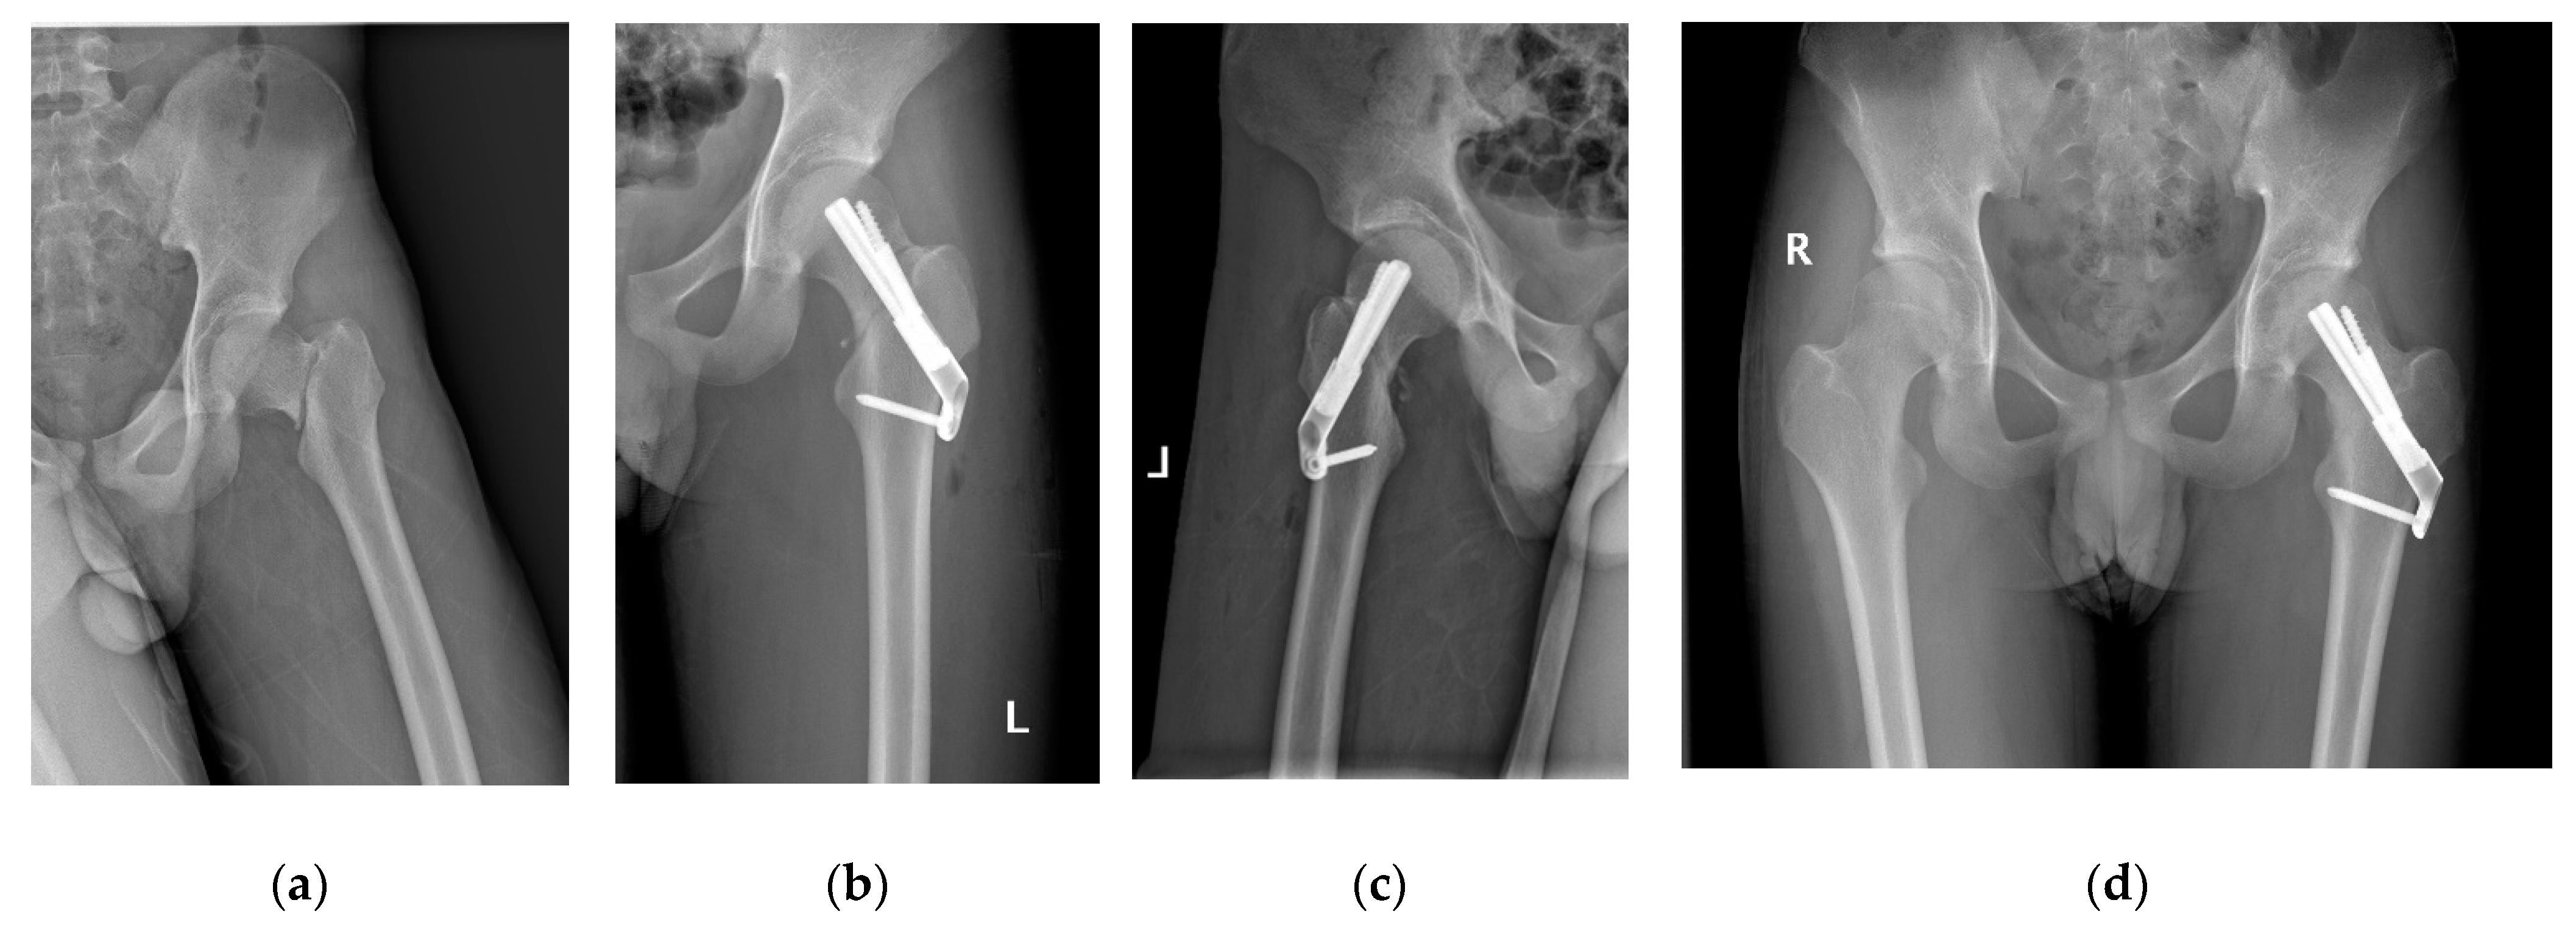

2.3. Femoral Neck System

2.4. Cannulated Compression Screw